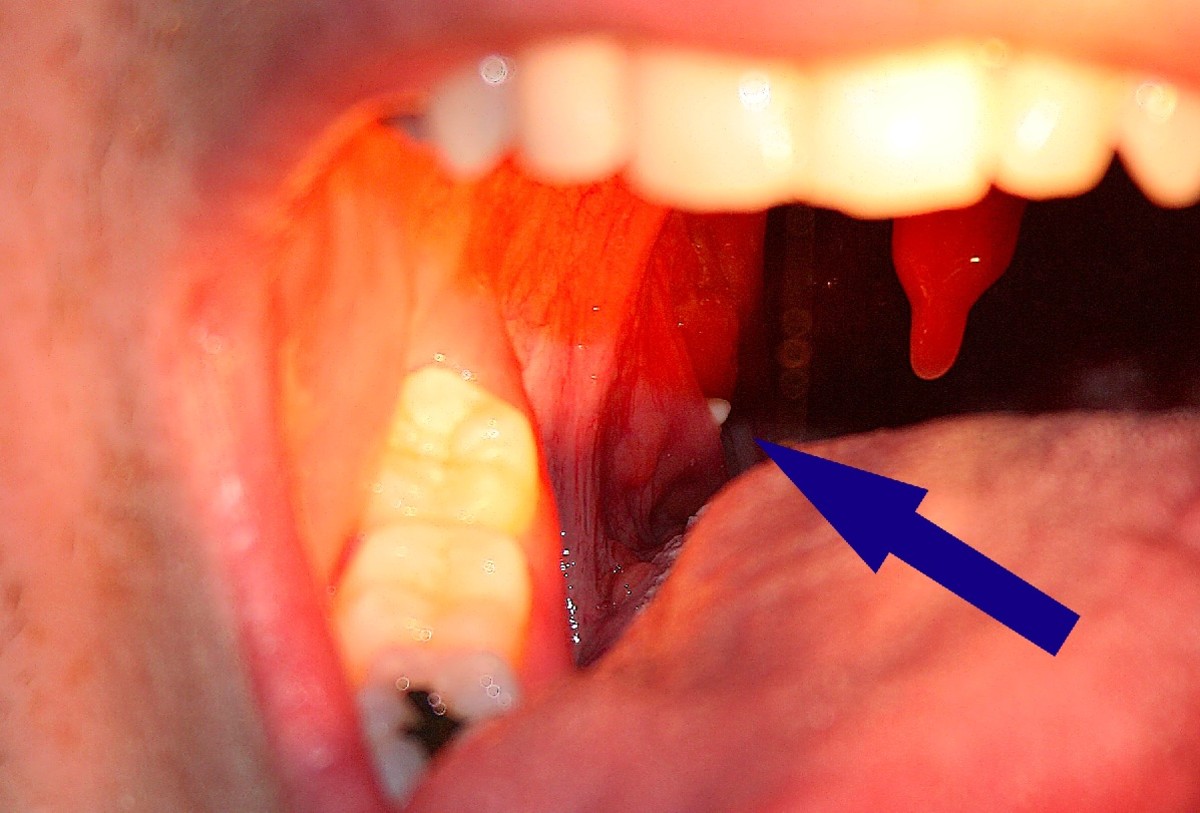

Symptoms of a pimple in the throat include soreness, pain when swallowing, difficulty breathing, and fever. In some cases, the pimple may burst and release pus or blood. If you experience any of these symptoms, it is important to see a doctor right away as they could be indicative of a more serious condition.

There are several tests that can be used to diagnose pimples in the throat. The most common test is a physical examination of the throat. This can be done by a doctor or other healthcare provider. A second common test is a culture of the bacteria that cause pimples in the throat. This test can be used to confirm the diagnosis and to identify the specific bacteria causing the infection. A third test that may be used is a blood test. This test can be used to look for antibodies to the bacteria that cause pimples in the throat.